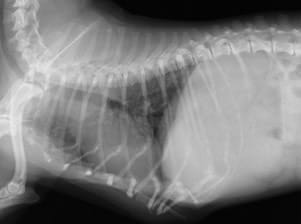

レントゲン検査

心臓の大きさや形の検査、さらに気管や肺の状態もチェックいたします。